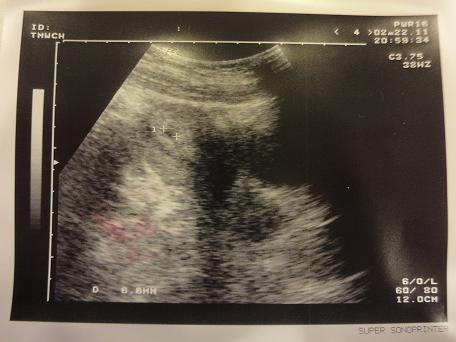

但今天去有照到胚胎耶!!!!!!!!

很明顯一個圓點

昨天查了資料 發現我照到的應該還是妊娠囊(還沒有心跳)

附上昨天照的超音波圖

請版上各位媽媽幫忙看看

感激不盡!!!